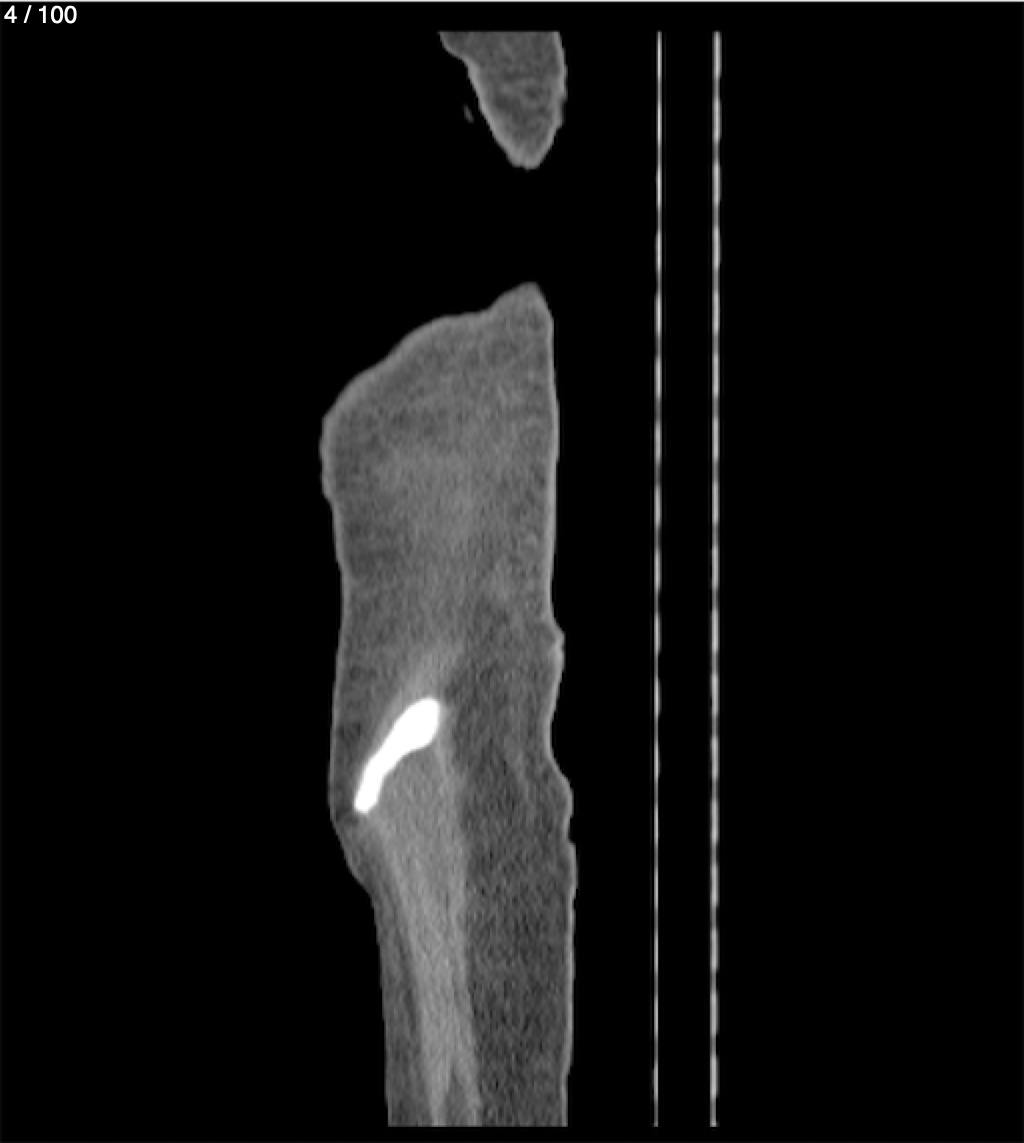

Hilda Geronimo Mendez 60A - T.C Abdomen Simple